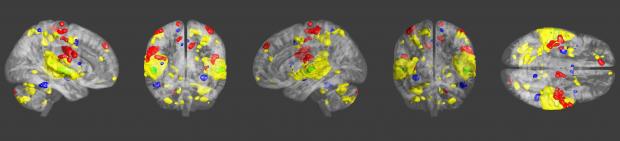

Die Untersuchungen zeigen, dass Schlagzeuger bessere Fähigkeiten zur Problemlösung haben und zusätzlich positive Auswirkungen auf die Allgemeinheit übertragen. Forscher am Karolinska Institut in Stockholm stellten fest, dass Drummer nach dem Spiel von rhythmischen Beats, bessere Ergebnisse bei einem 60 -Fragen- Intelligenz-Test erzielten konnten. Das würde bedeuten: Alle verschiedenen Teile eines Drum-Kits zu einem gleichmäßigen Takt zu formen, ist ein Ausdruck der inneren Problemlösungsfähigkeit.

Psychologie-Studien der Universität Washington zeigten, dass Probanden nach einer rhythmischen Licht- und Klangtherapie höhere Werte erzielten. Dieselbe Methode nutzten Medizinforscher einer Universität in Texas. Dabei konnten sie anhand der Klangtherapie bei ADHS-Kindern eine vergleichbare Wirkung erzielen, wie mit dem Medikament Ritalin. Sogar der IQ der Testprobanden schien sich zu verbessern.